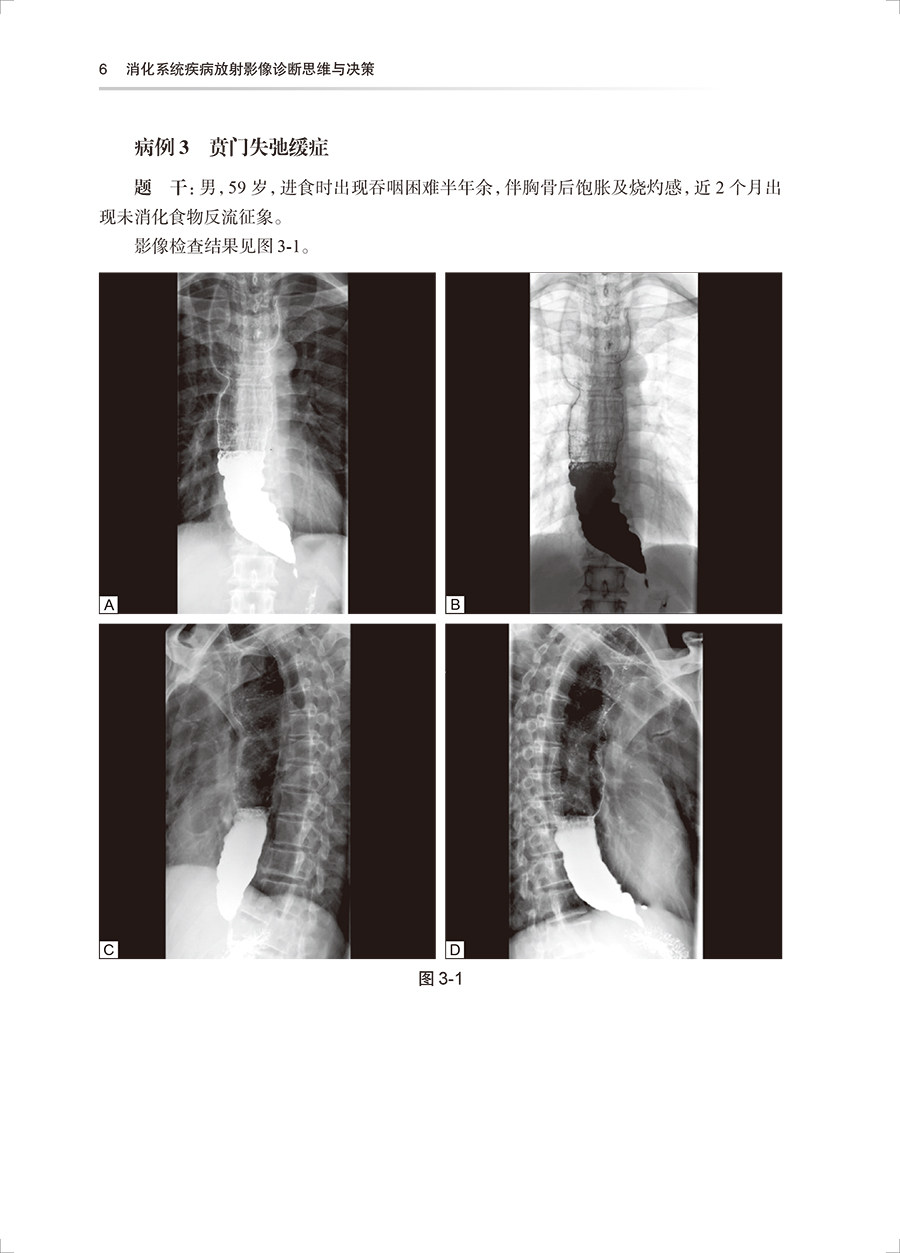

该丛书将由中国医师协会放射科医师分会候任会长梁长虹为第一总主编,中国工程院院士王振常为第二总主编,中华医学会放射学分会前任主任委员金征宇为第三总主编。中国医师协会放射科医师分会常务委员及委员担任分册主编。丛书共分为12个分册,各分册分别对应建立相应的题库(临床阅片实战场景、视频操作和专家视频解读)。内容围绕:放射诊断基本功、放射诊断报告书写、临床思维与决策、实践技能操作和临床医患沟通。其中临床思维与决策是核心问题。 本套书的第4到第10分册依系统分类,根据疾病的发病特点,分列不同的章,不同的章下分列不同的疾病病例。每一病例包括题目(临床资料,影像检查图,问题)、答案、结构化评分表。病例库内容包括病例全套的DICOM图像 + 病例讲解。